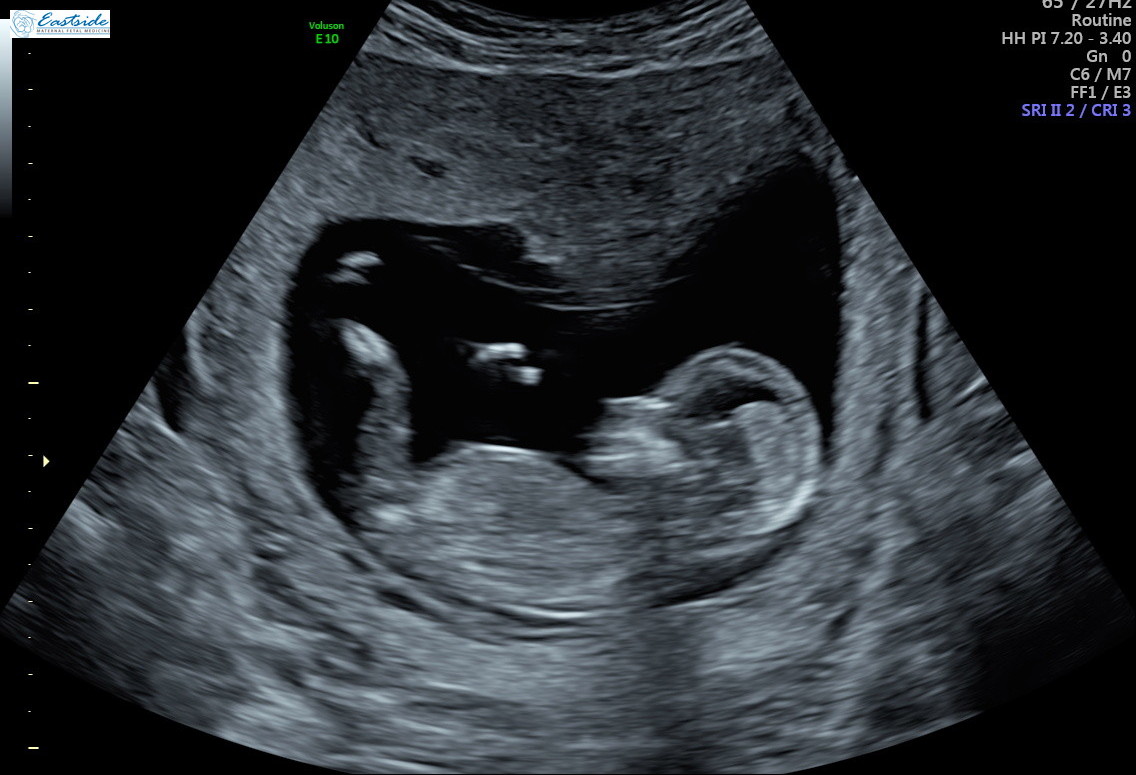

Purpose: The earlier the detection and diagnosis of congenital heart diseases CHDthe greater the clinical benefit; however, early fetal cardiac examination can be a challenge. Methods: The study was a prospective observational cohort study.How Accurate Are Dating Scans At 11 Weeks - How accurate are your pregnancy due dates?

No CHD were overlooked. Within patients with high BMI, early fetal echocardiography may be performed two weeks in advance, since it allows visualization of the fetal heart through the transvaginal route with a higher resolution in a large number of women, which is not feasible at 16 weeks. Abstract Purpose: The earlier the detection and diagnosis of congenital heart diseases CHDthe greater the clinical benefit; however, early fetal http://lifescienceglobal.com/review/dating-sites-for-hiv-singles/gay-dating-events-in-nyc.php examination can be a challenge.